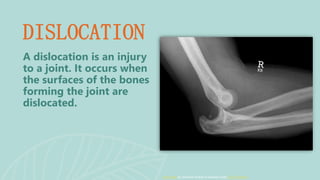

DISLOCATION

A dislocation is an injury

to a joint. It occurs when

the surfaces of the bones

forming the joint are

dislocated.